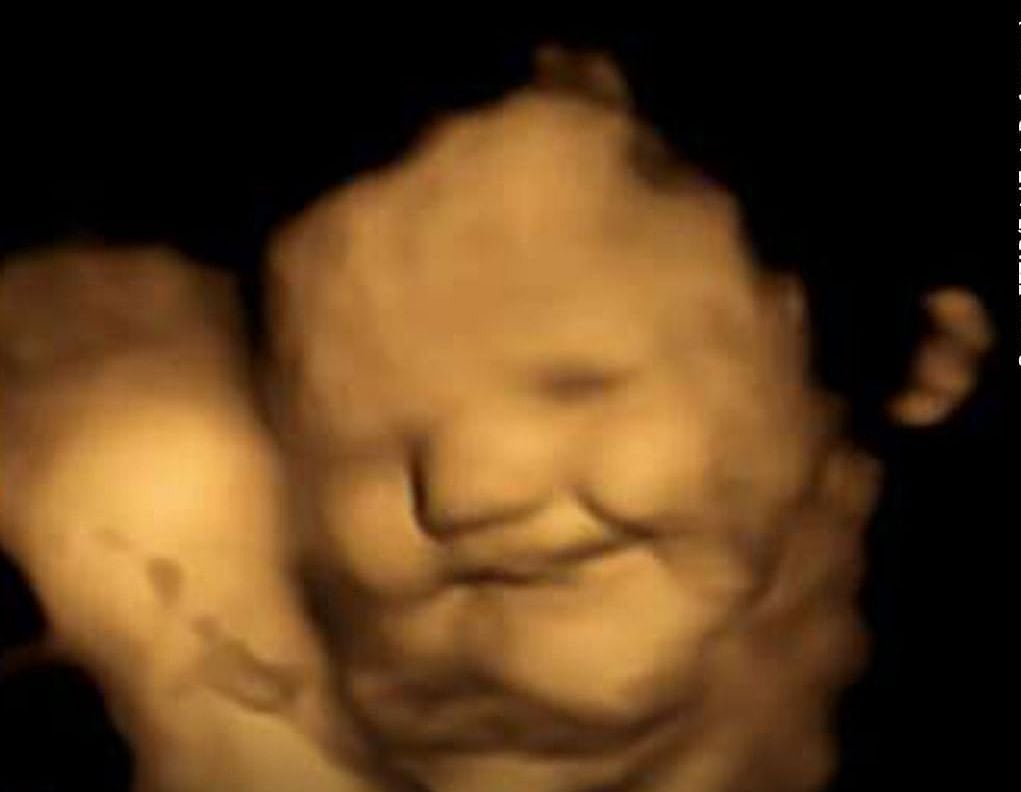

এ প্রশ্ন নিয়েই যুক্তরাজ্যের ডারহাম বিশ্ববিদ্যালয়ের একটি গবেষণা সম্প্রতি প্রকাশিত হয়েছে। এ গবেষণায় অংশ নেন ৮ ও ৯ মাসের গর্ভবতী ১০০ নারী। এই নারীদের বিভিন্ন স্বাদের ক্যাপসুল খাওয়ানো হয়। আর দেখা হয়, গর্ভের বাচ্চার মুখভঙ্গি। পরে এই নারীদের গাজরের জুস আর পাতাকপির জুস দেওয়া হয়। গাজরের জুস খাওয়ার পর দেখা গেছে, বাচ্চাদের মুখের ভঙ্গি হয় অনেকটা হাসিমুখের মতো। আর পাতাকপির জুস খাওয়ানোর পর তারা ‘ক্রাইং ফেস’ বা কান্নার মতন চেহারা করে।